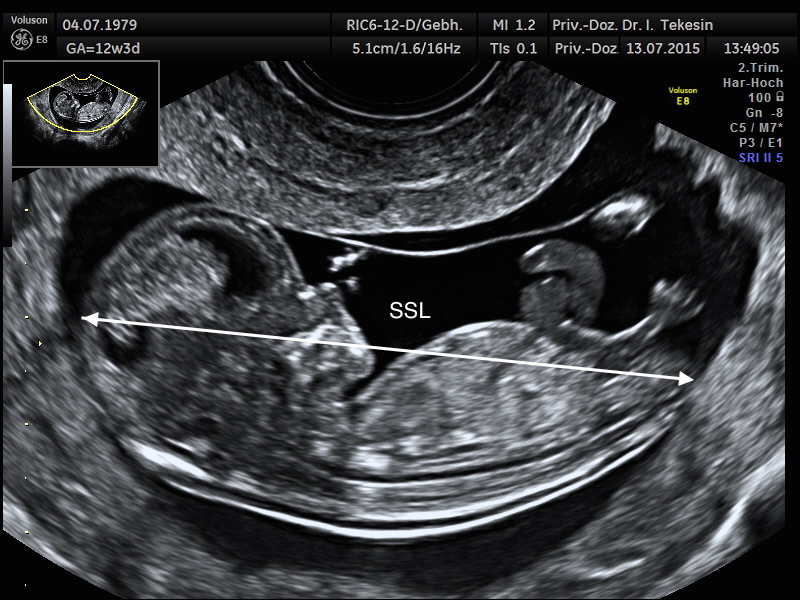

Scheitelsteißlänge (SSL) in der 13. Schwangerschaftswoche (SSW)

Scheitel-Steiß-Länge (SSL) in der 13. SSW